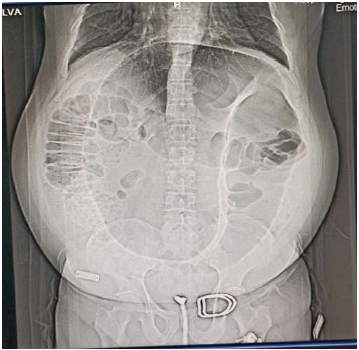

Um paciente de 60 anos de idade deu entrada no pronto-socorro sem acompanhante, com histórico de dor abdominal e parada de eliminação de flatos e fezes há três dias. Referiu que, no último mês, foi atendido duas vezes na mesma unidade, por episódios semelhantes. Ao exame físico, apresentou-se eupneico, estável hemodinâmicamente, com abdome globoso, timpânico à percussão, sem irritação peritoneal e com ECG 15.

Os exames laboratoriais evidenciaram leuco 7.000, Hb = 12 e creatina = 0,9, e o exame de raios X resultou na imagem a seguir.

Assinale a alternativa que indica a melhor conduta para esse caso nesse momento.

Um paciente de 60 anos de idade deu entrada no pronto-socorro sem acompanhante, com histórico de dor abdominal e parada de eliminação de flatos e fezes há três dias. Referiu que, no último mês, foi atendido duas vezes na mesma unidade, por episódios semelhantes. Ao exame físico, apresentou-se eupneico, estável hemodinâmicamente, com abdome globoso, timpânico à percussão, sem irritação peritoneal e com ECG 15.

Os exames laboratoriais evidenciaram leuco 7.000, Hb = 12 e creatina = 0,9, e o exame de raios X resultou na imagem a seguir.

Com base no caso clínico apresentado, assinale a alternativa que corresponde à hipótese diagnóstica mais provavel.